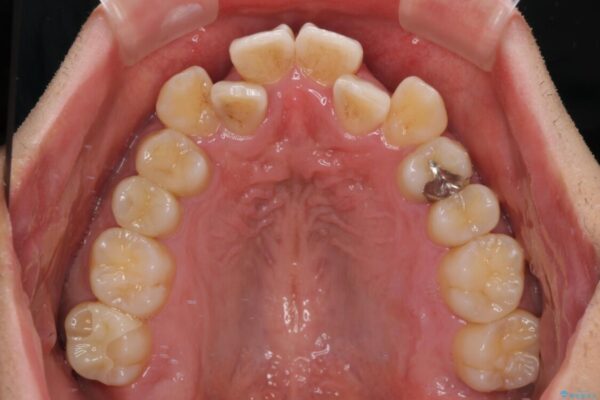

「八重歯を治したい」とご相談いただいた患者様の症例をご紹介します。

上下の前歯部に強い叢生(ガタガタの歯並び)があり、そのまま歯を並べると出っ歯になってしまう可能性がありました。

治療前

• 八重歯と前歯のガタガタを抜歯矯正で治療|クリアブラケット使用例 治療前画像